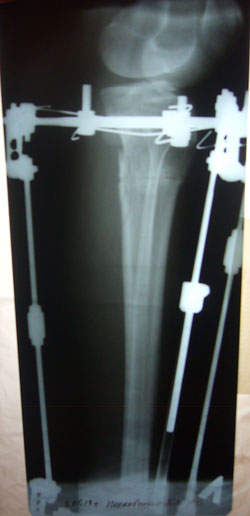

рентгеновские снимки от 03.01.2013г.

2 месяца с момента операции.

P1060108.JPG

P1060107.JPG

P1060106.JPG